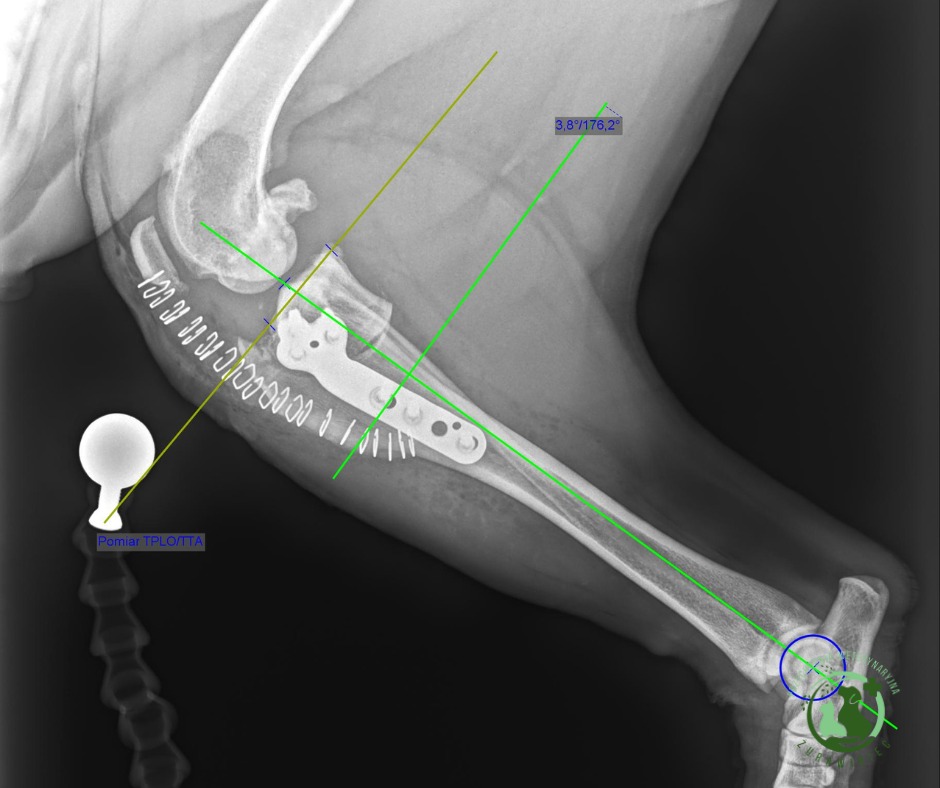

Leczenie uszkodzeń więzadła krzyżowego doczaszkowego

W naszej placówce przeprowadzamy zabiegi leczenia zerwania i uszkodzenia więzadła krzyżowego doczaszkowego, stosując sprawdzone procedury TPLO oraz technikę szwu bocznego. Dobór metody zależy od wielkości, wieku i aktywności pacjenta.